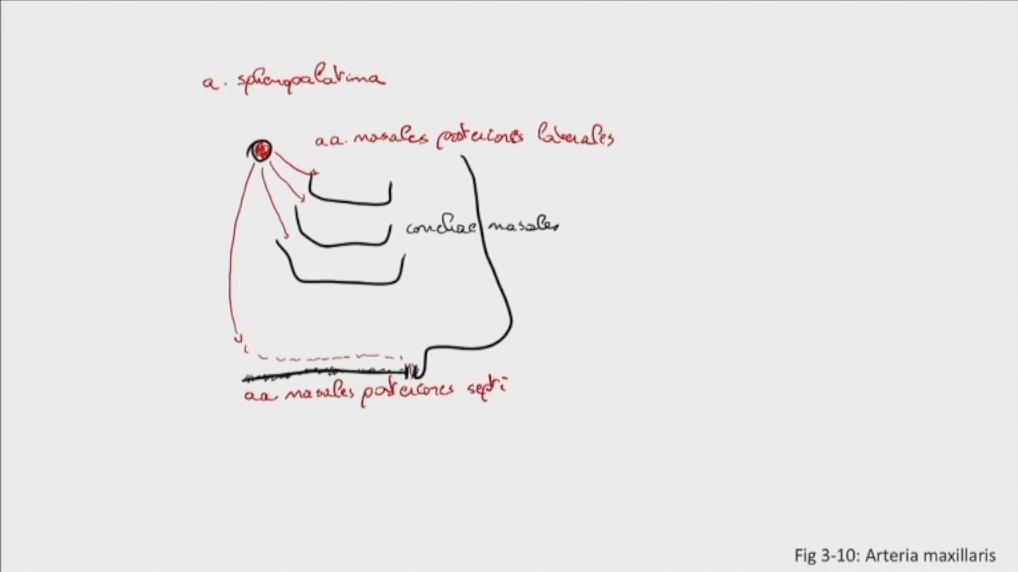

Fig 3.10b: a. maxillaris - sfenomaxillair deel - neusholte

|

|